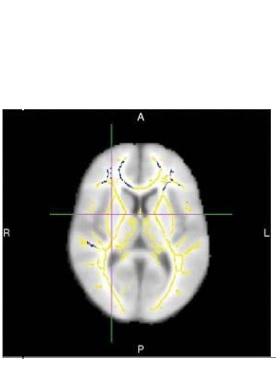

Des zones d'anisotropie fractionnelle réduite, un marqueur à l'imagerie par tenseur de diffusion des lésions de la substance blanche (sur le visuel ci-dessous en bleu) constituent un marqueur de prédiction très précis de la maladie d'Alzheimer, souligne cette recherche, menée auprès d’une quarantaine de patients, par une équipe de de l'Université de Washington à Saint-Louis. Des travaux présentés au Congrès annuel de la Radiological Society of North America qui soutiennent l’efficacité de cette technique IRM, en comparaison d’autres tests cliniques, pour détecter les patients à risque élevé de développer la maladie d'Alzheimer.

L'examen par imagerie par tenseur de diffusion, une technique d'IRM, permet d’évaluer le mouvement des molécules d'eau (anisotropie) le long des voies de la substance blanche. Et de voies mal connectées, résultent des troubles cognitifs caractéristiques de la maladie. L'anisotropie fractionnelle, cette mesure de la manière dont les molécules d'eau se déplacent le long des voies de la substance blanche est l’une des différentes mesures d'intégrité de la substance blanche. Une valeur supérieure indique que l'eau se déplace de manière plus ordonnée le long des voies, tandis qu'une valeur plus faible signifie que les voies sont probablement endommagées.

Ici, les chercheurs quantifient les différences d’anisotropie fractionnelle obtenue par DTI chez 30 patients éprouvant un déclin cognitif normal lié à l’âge ou une déficience cognitive légère voire un déclin cognitif caractéristique d'Alzheimer, par rapport à 30 personnes témoins qui ne développent pas de démence. Alors qu’environ la moitié des patients ont développé la maladie d'Alzheimer, l’examen par DTI identifie des différences quantifiables dans le cerveau de ces patients :

- Les participants qui ont développé la maladie présentent un taux d'L'anisotropie fractionnelle inférieur à celui des autres patients, ce qui suggère des dommages à la substance blanche ;

- ces patients présentent ont également réductions statistiquement significatives dans certaines voies de la substance blanche frontale.